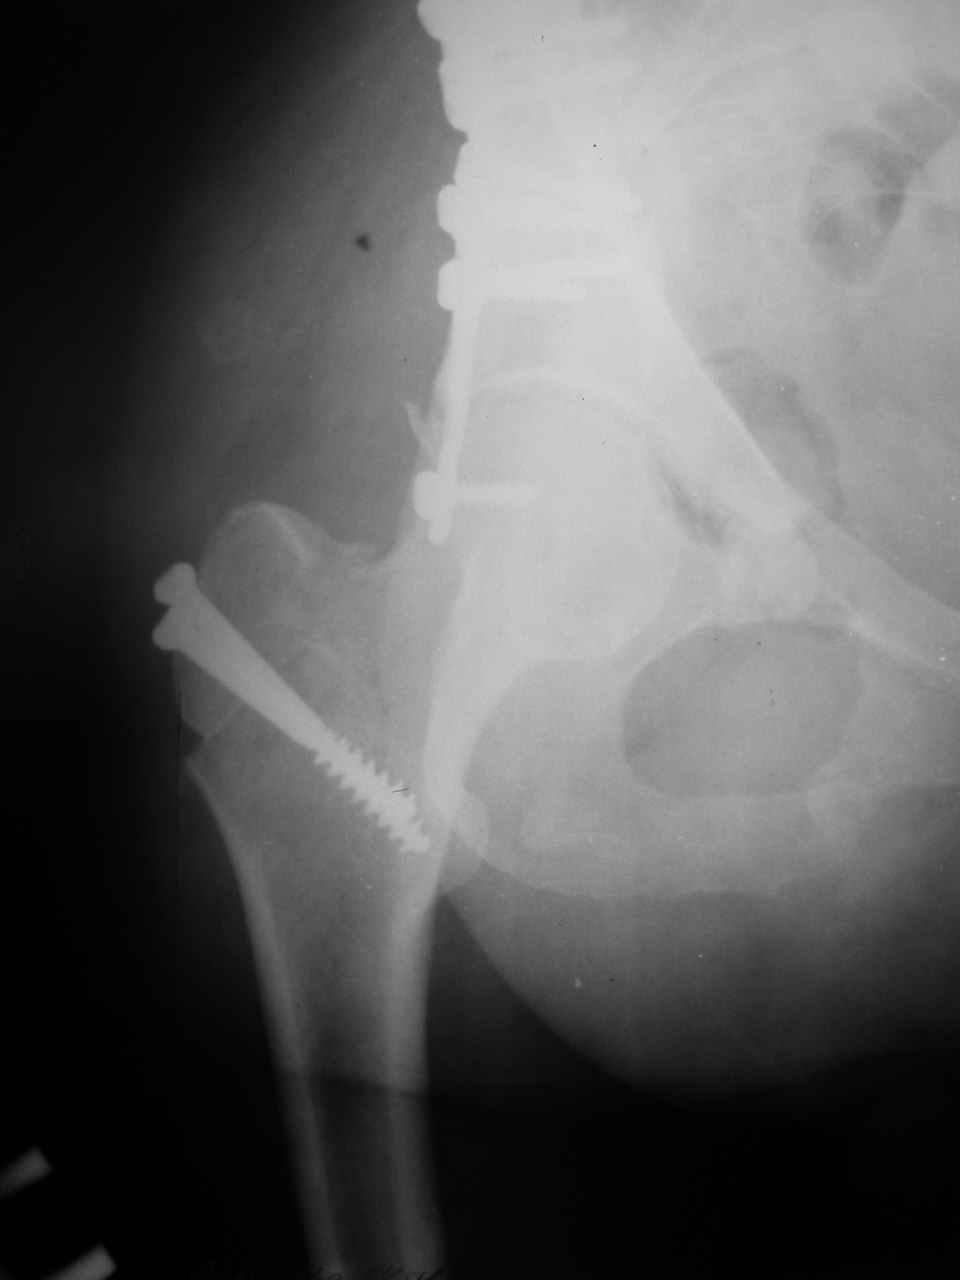

Вопрос доступа к вертлужной впадине при остеосинтезе задача не простая. Конечно, у Летурнеля и Тайла всё давно описано, нам остается только брать на вооружение. Но сами понимаете, что не бывает двух одинаковых ситуаций, поэтому в каждом случае вопрос решается сугубо индивидуально. Наша главная цель - восстановить анатомию с нанесением минимальной дополнительной травмы тазобедреннному суставу, думаю с этим никто не поспорит. Расширенный илиофеморальный доступ уж слишком травматичен (как сказал один коллега "таз лежит отдельно, больной отдельно").Стоит ли делать из пациента анатомический препарат для того чтобы легче ориентироваться. Да и нужно ли собирать всю "мозаику"? Мы применяли при таких операциях своеобразную операционную хитрость - сначала устраняли грубое смещение крыла под гребнем с фиксацией так называемой "плавающей" пластиной (временно фиксированной на двух винтах)- доступ или продлевали боковой, или делали небольшой дополнительный разрез над гребнем. Это позволяло устранить грубое смещение и захождение отломков тела повздошной кости, что значительно облегчало репозицию и остеосинтез впадины над сводом. Основное внимание конечно же уделяли нагружаемому задне-верхнему отделу. Сообщите ваш адрес, пришлю схемы и рентгенограммы.